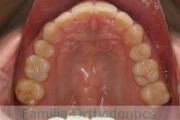

No.22V-029

- 叢生

- 上顎前突

- 19歳

- 男性

- 上:

- 8448

- 下:

- 主な使用装置:

- FEA 022

- 治療にかかった費用:

- 92万円

でこぼこを治したいということで来院されました。上下左右から親知らずも第一小臼歯も抜歯が必要で、歯科矯正アンカースクリューを併用して大臼歯を後ろに引っ張りながらの治療でした。3年弱、35回程度の通院が必要でした。

叢生が著しく、後戻りのリスクがあります。またアンカースクリューが必須のため、もしもスクリューが安定しないと、治療が難しく長くなってしまう恐れがありましたが、幸い脱落は見られませんでした。